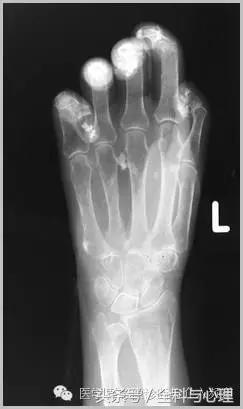

4、痛风石

为尿酸盐沉积形成,发生在关节周围软组织、包括韧带、肌腱、滑囊,眼、耳、鼻、喉、皮肤, 50%的钙化为X线平片可见。

软组织钙化与骨化,软组织钙化和骨质增生

痛风石,可见软组织肿胀及钙化灶。